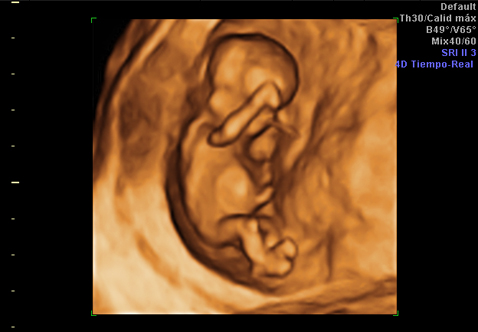

¿Qué es una ecografía en 4D?

Ventajas de realizar la ecografía en cuatro dimensiones y en qué semana del embarazo se recomienda

Todas las familias están deseando conocer la carita de su futuro bebé, y hoy en día muchas madres recurren a las ecografías en 4D, que ofrecen imágenes realmente impresionantes. A quién no se le ha caído la baba ante esas pantallas que nos muestran al feto como si ya estuviera fuera… Pero, ¿sabemos en qué consiste ...

Un nuevo ecógrafo 3D/4D muestra imágenes más nítidas

Se trata un equipo de alta gama especializado en aplicaciones obstétricas

Desde que aparecieron las primeras ecografías en 4D el mundo de la obstetricia se revolucionó por completo. Y es que, más allá de las implicaciones diagnósticas que pueda tener esta prueba, para una madre, desde el punto de vista psicológic...